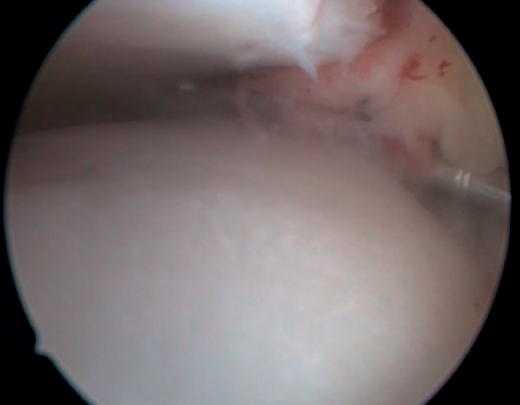

El ligamento de Bassett debe conservarse siempre que no tenga un aspecto patológico, descartando engrosamientos, roturas parciales o lesiones recíprocas en la superficie anterolateral del astrágalo (Figura 6), que se asocian a inestabilidades anterolaterales o rotatorias. La inserción peroneal se usa como referencia para localizar la inserción distal del LTFA. Debe inspeccionarse el ligamento deltoideo en la gotera medial en caso de sospecha de inestabilidad rotatoria asociada. Durante la artroscopia, se puede realizar una reparación directa de los ligamentos mediante suturas y anclajes.

Figura 6. Surco producido por el roce de la cúpula talar con el ligamento de Bassett, visible tras la resección de este. El ligamento presentaba una rotura parcial y un engrosamiento cicatricial.